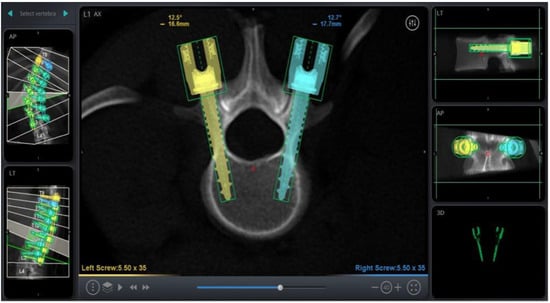

RAN technology relies on three-dimensional imaging and computer software to plan appropriate pedicle screw placement based on the patient’s anatomy (Figure 1). Once the patient’s anatomy is registered to the system, the robotic arm is sent to each screw placement trajectory location at the selected vertebral levels. Instruments are then sent through the robotic arm to guide placement, with navigation confirming positions in real time (Figure 2).

Figure 1. Screw Trajectory Planning on RAN Platform.